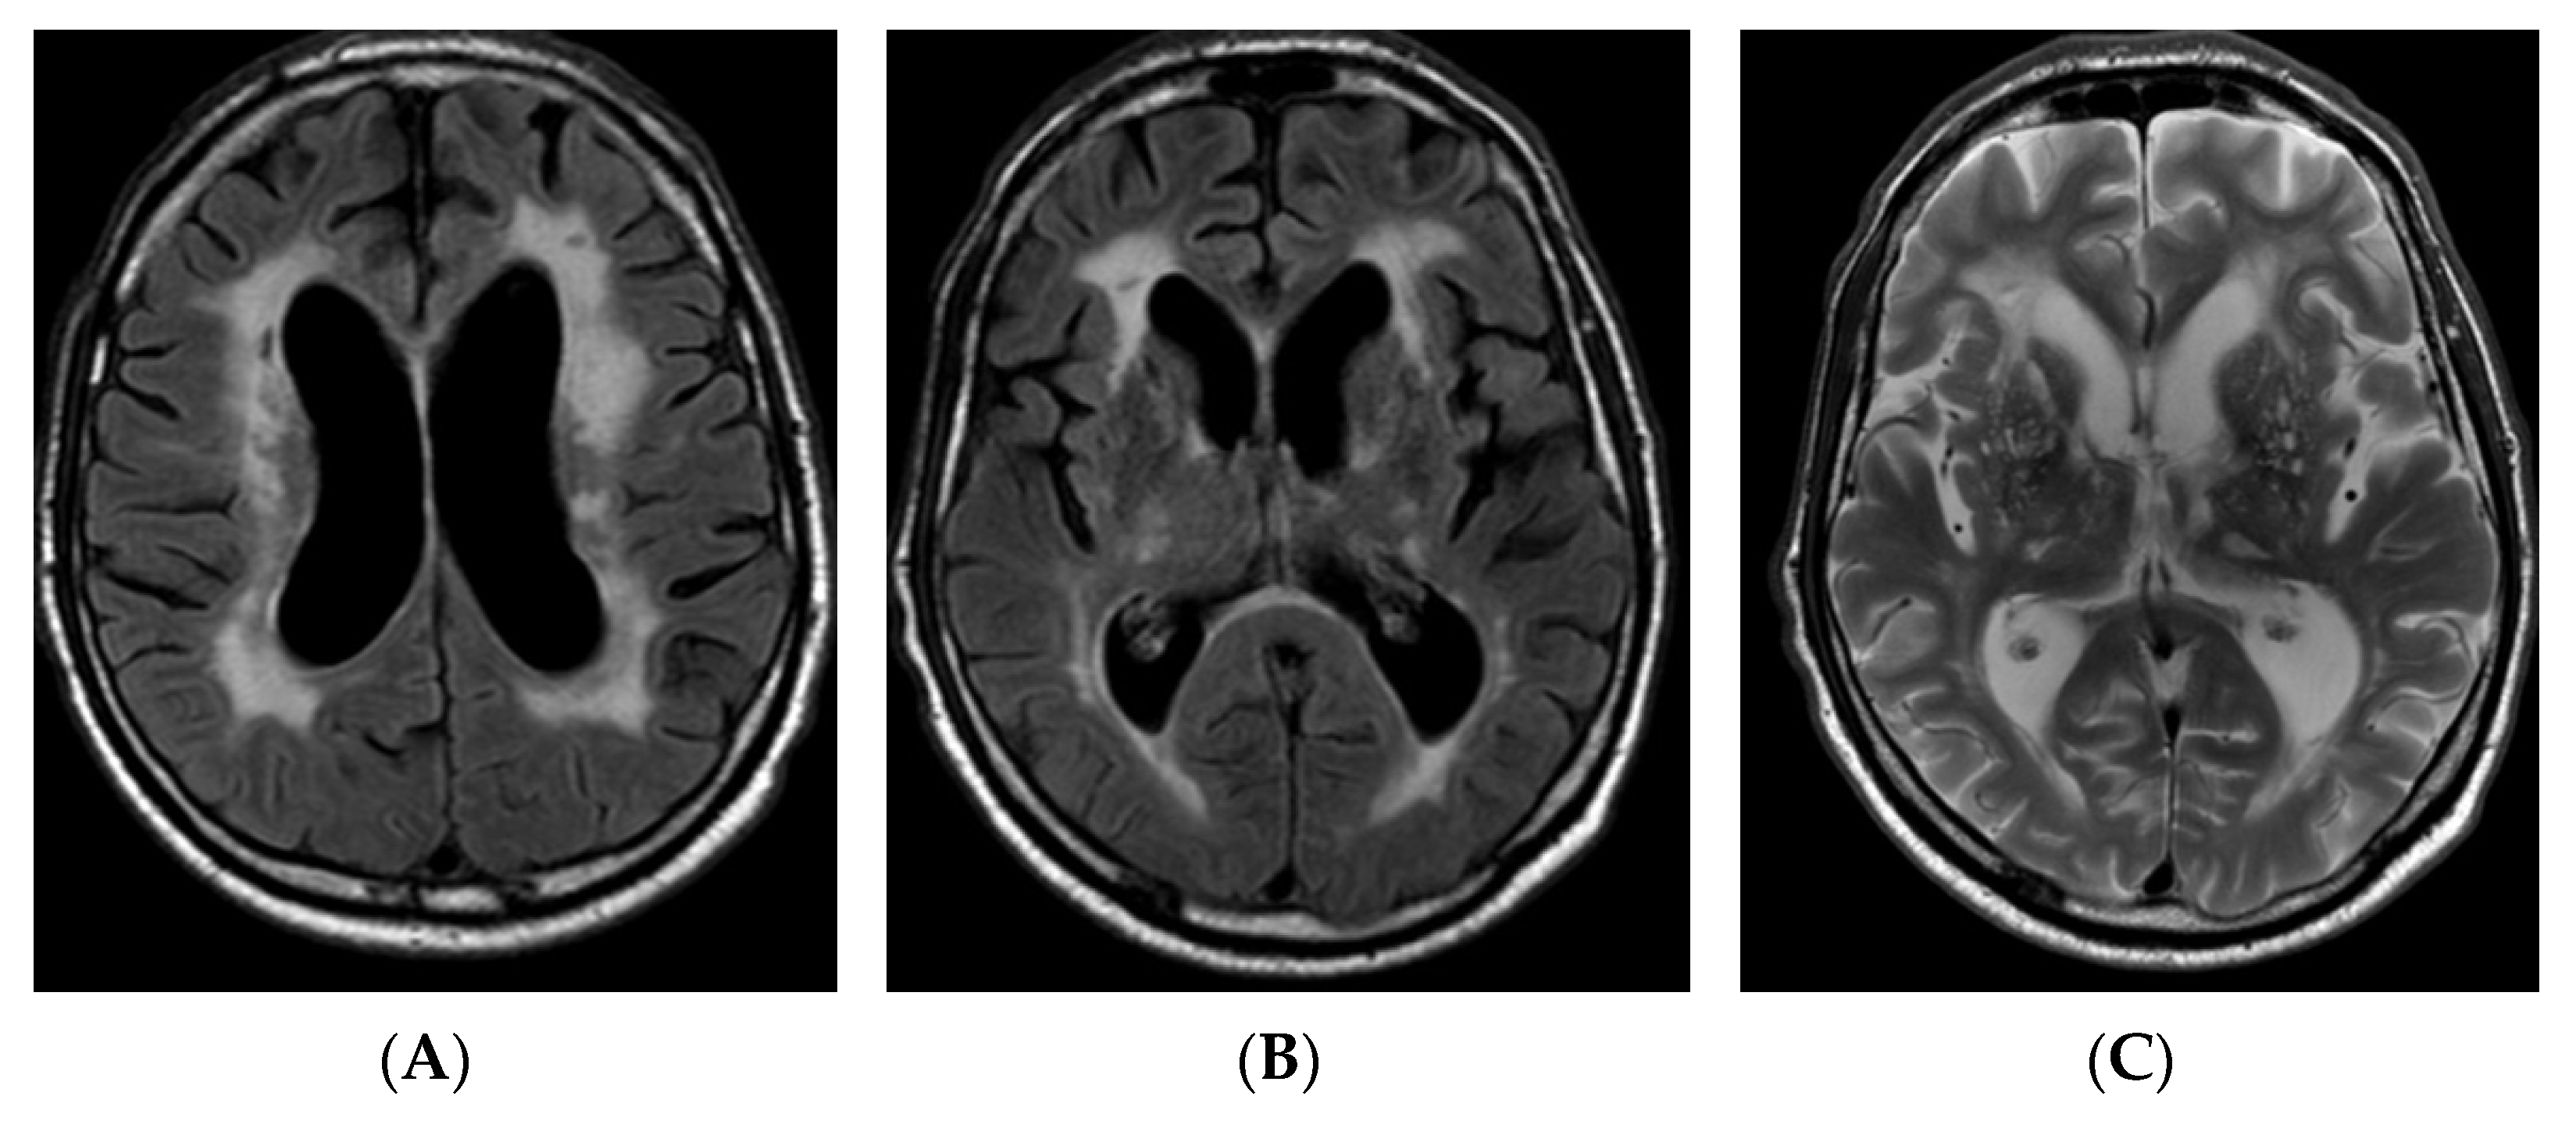

A 59-year-old Lithuanian male presented to our department due to deterioration of cognitive functions that had been observed for 2–3 years and gotten worse over the past three days. The patient could not perform some simple tasks in everyday life and lost his previous interests. He maintained some independence though, such as being able to go to the supermarket and do housework unsupervised. Past medical history was significant for dyslipidaemia, arterial hypertension, and stroke at the age of 36 with mild right hemiparesis. He also experienced several episodes of aphasia, which could be considered as transient ischemic attacks (TIAs). The patient had a history of smoking for a long time. He was born full-term and healthy; his parents, four siblings, and two offspring did not have any relevant health problems and no hereditary diseases were identified among family members. On neurological examination, mild bilateral dysmetria was observed and the mental examination revealed executive dysfunction and pronounced cognitive slowing. Mini–Mental State Examination (MMSE) score was 25, Frontal Assessment Battery (FAB) score was 5, phonemic fluency (words beginning with P) was 4 in one minute, and semantic fluency (animals) was 3 in one minute. Laboratory blood tests revealed significant dyslipidaemia (total cholesterol level—7.55 mmol/L, low-density lipoprotein level—5.82 mmol/L). Cerebrospinal fluid analysis was unremarkable. Low grade bilateral internal and external carotid artery stenosis was detected on carotid ultrasound. Brain magnetic resonance imaging (MRI) revealed communicating hydrocephalus, most likely due to brain atrophy and secondary brain changes, with no obvious cause of obstruction in the ventricles (Huckman index was equal to 66; the width of the third ventricle was equal to 10 mm), and extensive leukoencephalopathy, Fazekas scale score 2–3, lacunar lesions in the dorsal part of pons, thalamus bilaterally, and right cerebellar hemisphere (Figure 1).

Figure 1. Axial T2-weighted image (A) and FLAIR axial images (B,C) of brain MRI demonstrating subcortical and periventricular T2/T2 dark-fluid hyperintensities, Fazekas scale score 2–3, lacunar lesions in the thalamus bilaterally, and hydrocephalus (HI—66). FLAIR: fluid attenuated inversion recovery; MRI: magnetic resonance imaging, HI: Huckman index.